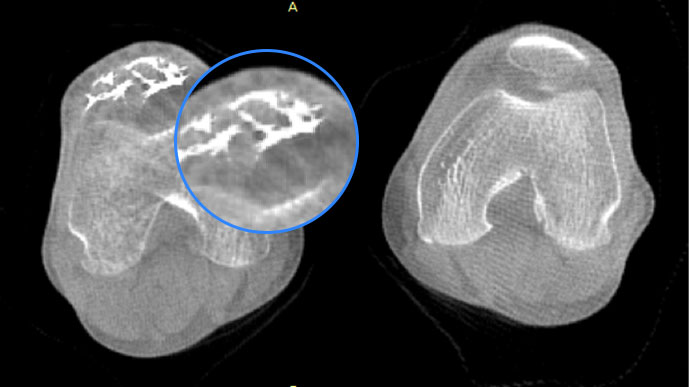

膝關(guān)節(jié)

智能金屬偽影抑制算法

關(guān)閉金屬偽影校正

開啟金屬偽影校正